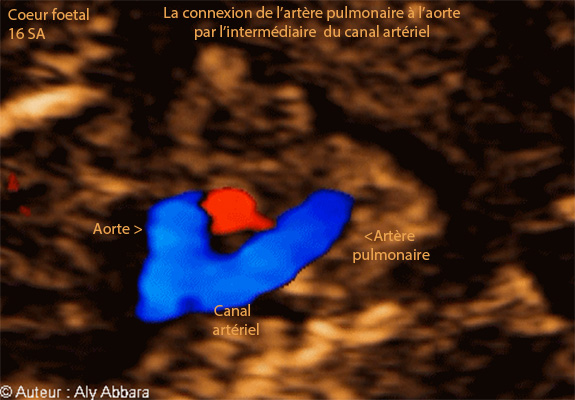

Images échographiques cardiaques montrant la communication normale et observable entre l'artère pulmonaire et l'aorte par l'intermédiaire du canal artériel.

l'artère pulmonaire sur cette coupe peut être confondue avec une communication interventriculaire.

Foetus de16 SA.